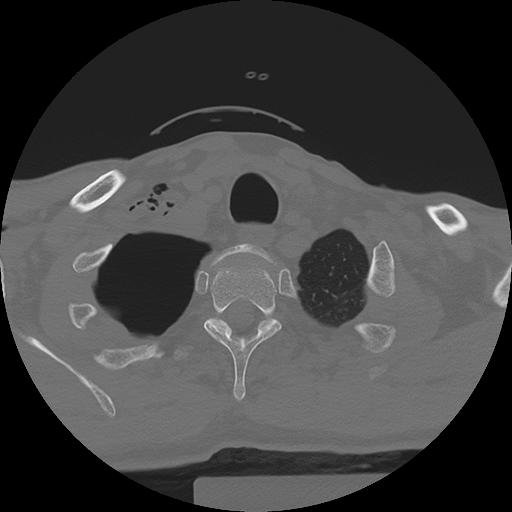

11 HUESO,,Axial,2.0,HUESO,,